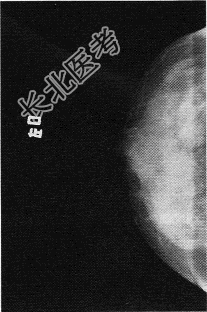

- 单项选择题患者女,67岁。发现乳腺包块1个月余, 伴乳头溢液,X线图像如下, 最有可能诊断为

D、乳腺癌